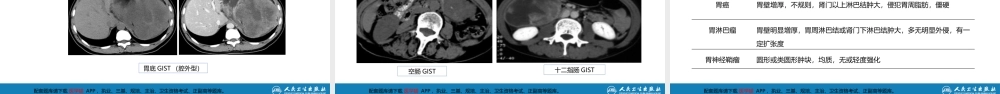

配套题库请下载医学猫APP,执业、三基、规培、主治、卫生资格考试、正副高等题库。作者:刘玉村单位:北京大学医学部胃十二指肠疾病第三十四章配套题库请下载医学猫APP,执业、三基、规培、主治、卫生资格考试、正副高等题库。重点难点熟悉了解掌握胃肠间质瘤的临床表现和治疗原则胃肠间质瘤的病因和诊断方法胃肠间质瘤的靶向治疗配套题库请下载医学猫APP,执业、三基、规培、主治、卫生资格考试、正副高等题库。第三节(二)胃肠道间质瘤配套题库请下载医学猫APP,执业、三基、规培、主治、卫生资格考试、正副高等题库。名称的变革胃肠道间叶细胞又称间充质细胞,源于中胚层,广泛存在于胃肠道管壁的各层组织中,包括黏膜层、黏膜下层、肌层、浆膜层及其系膜间叶细胞有多项分化潜能,可以进一步分化为纤维母细胞、肌纤维母细胞、脂肪细胞、血管内皮细胞和滑膜细胞等1940—1960年,由于医学发展的局限性,种类繁多、形态复杂的胃肠道间叶来源的肿瘤被误认为平滑肌瘤或神经源性肿瘤胃肠道间质瘤的概念外科学(第9版)配套题库请下载医学猫APP,执业、三基、规培、主治、卫生资格考试、正副高等题库。胃肠道间质瘤的概念名称的变革1970年,电镜技术的应用发现只有很少的此类肿瘤具有平滑肌分化1983年,Mazur和Clark利用电镜和免疫组化技术发现,这组肿瘤的抗原表达和超微结构既无平滑肌分化又无神经源性分化,而是一种非定向分化的间质瘤,于是首先将其命名为“胃间质瘤-GastricStromalTumours“外科学(第9版)配套题库请下载医学猫APP,执业、三基、规培、主治、卫生资格考试、正副高等题库。胃肠道间质瘤的概念HirotaS,etal.Gain-of-functionmutationsofc-kitinhumangastrointestinalstromaltumors.Science,1998,279(5350):577-580.名称的变革由于缺乏绝对的诊断标志,与雪旺细胞瘤、平滑肌肉瘤等胃肠道间质性肿瘤相混淆1998年,Hirota等通过分子生物学研究发现胃肠道间质瘤特异性表达c-kit酪氨酸激酶受体,可用c-kit基因编码KIT蛋白(CD117)单克隆抗体检测,为诊断GIST确定了标准外科学(第9版)配套题库请下载医学猫APP,执业、三基、规培、主治、卫生资格考试、正副高等题库。胃肠道间质瘤的概念定义是一组独立起源于胃肠道间质干细胞(Cajal细胞)的肿瘤,由未分化或多能的梭形或上皮样细胞组成,免疫组化通常过表达CD117(c-KIT基因编码KIT蛋白的抗原性抗体)和DOG-1,属于消化道间叶性肿瘤外科学(第9版)配套题...